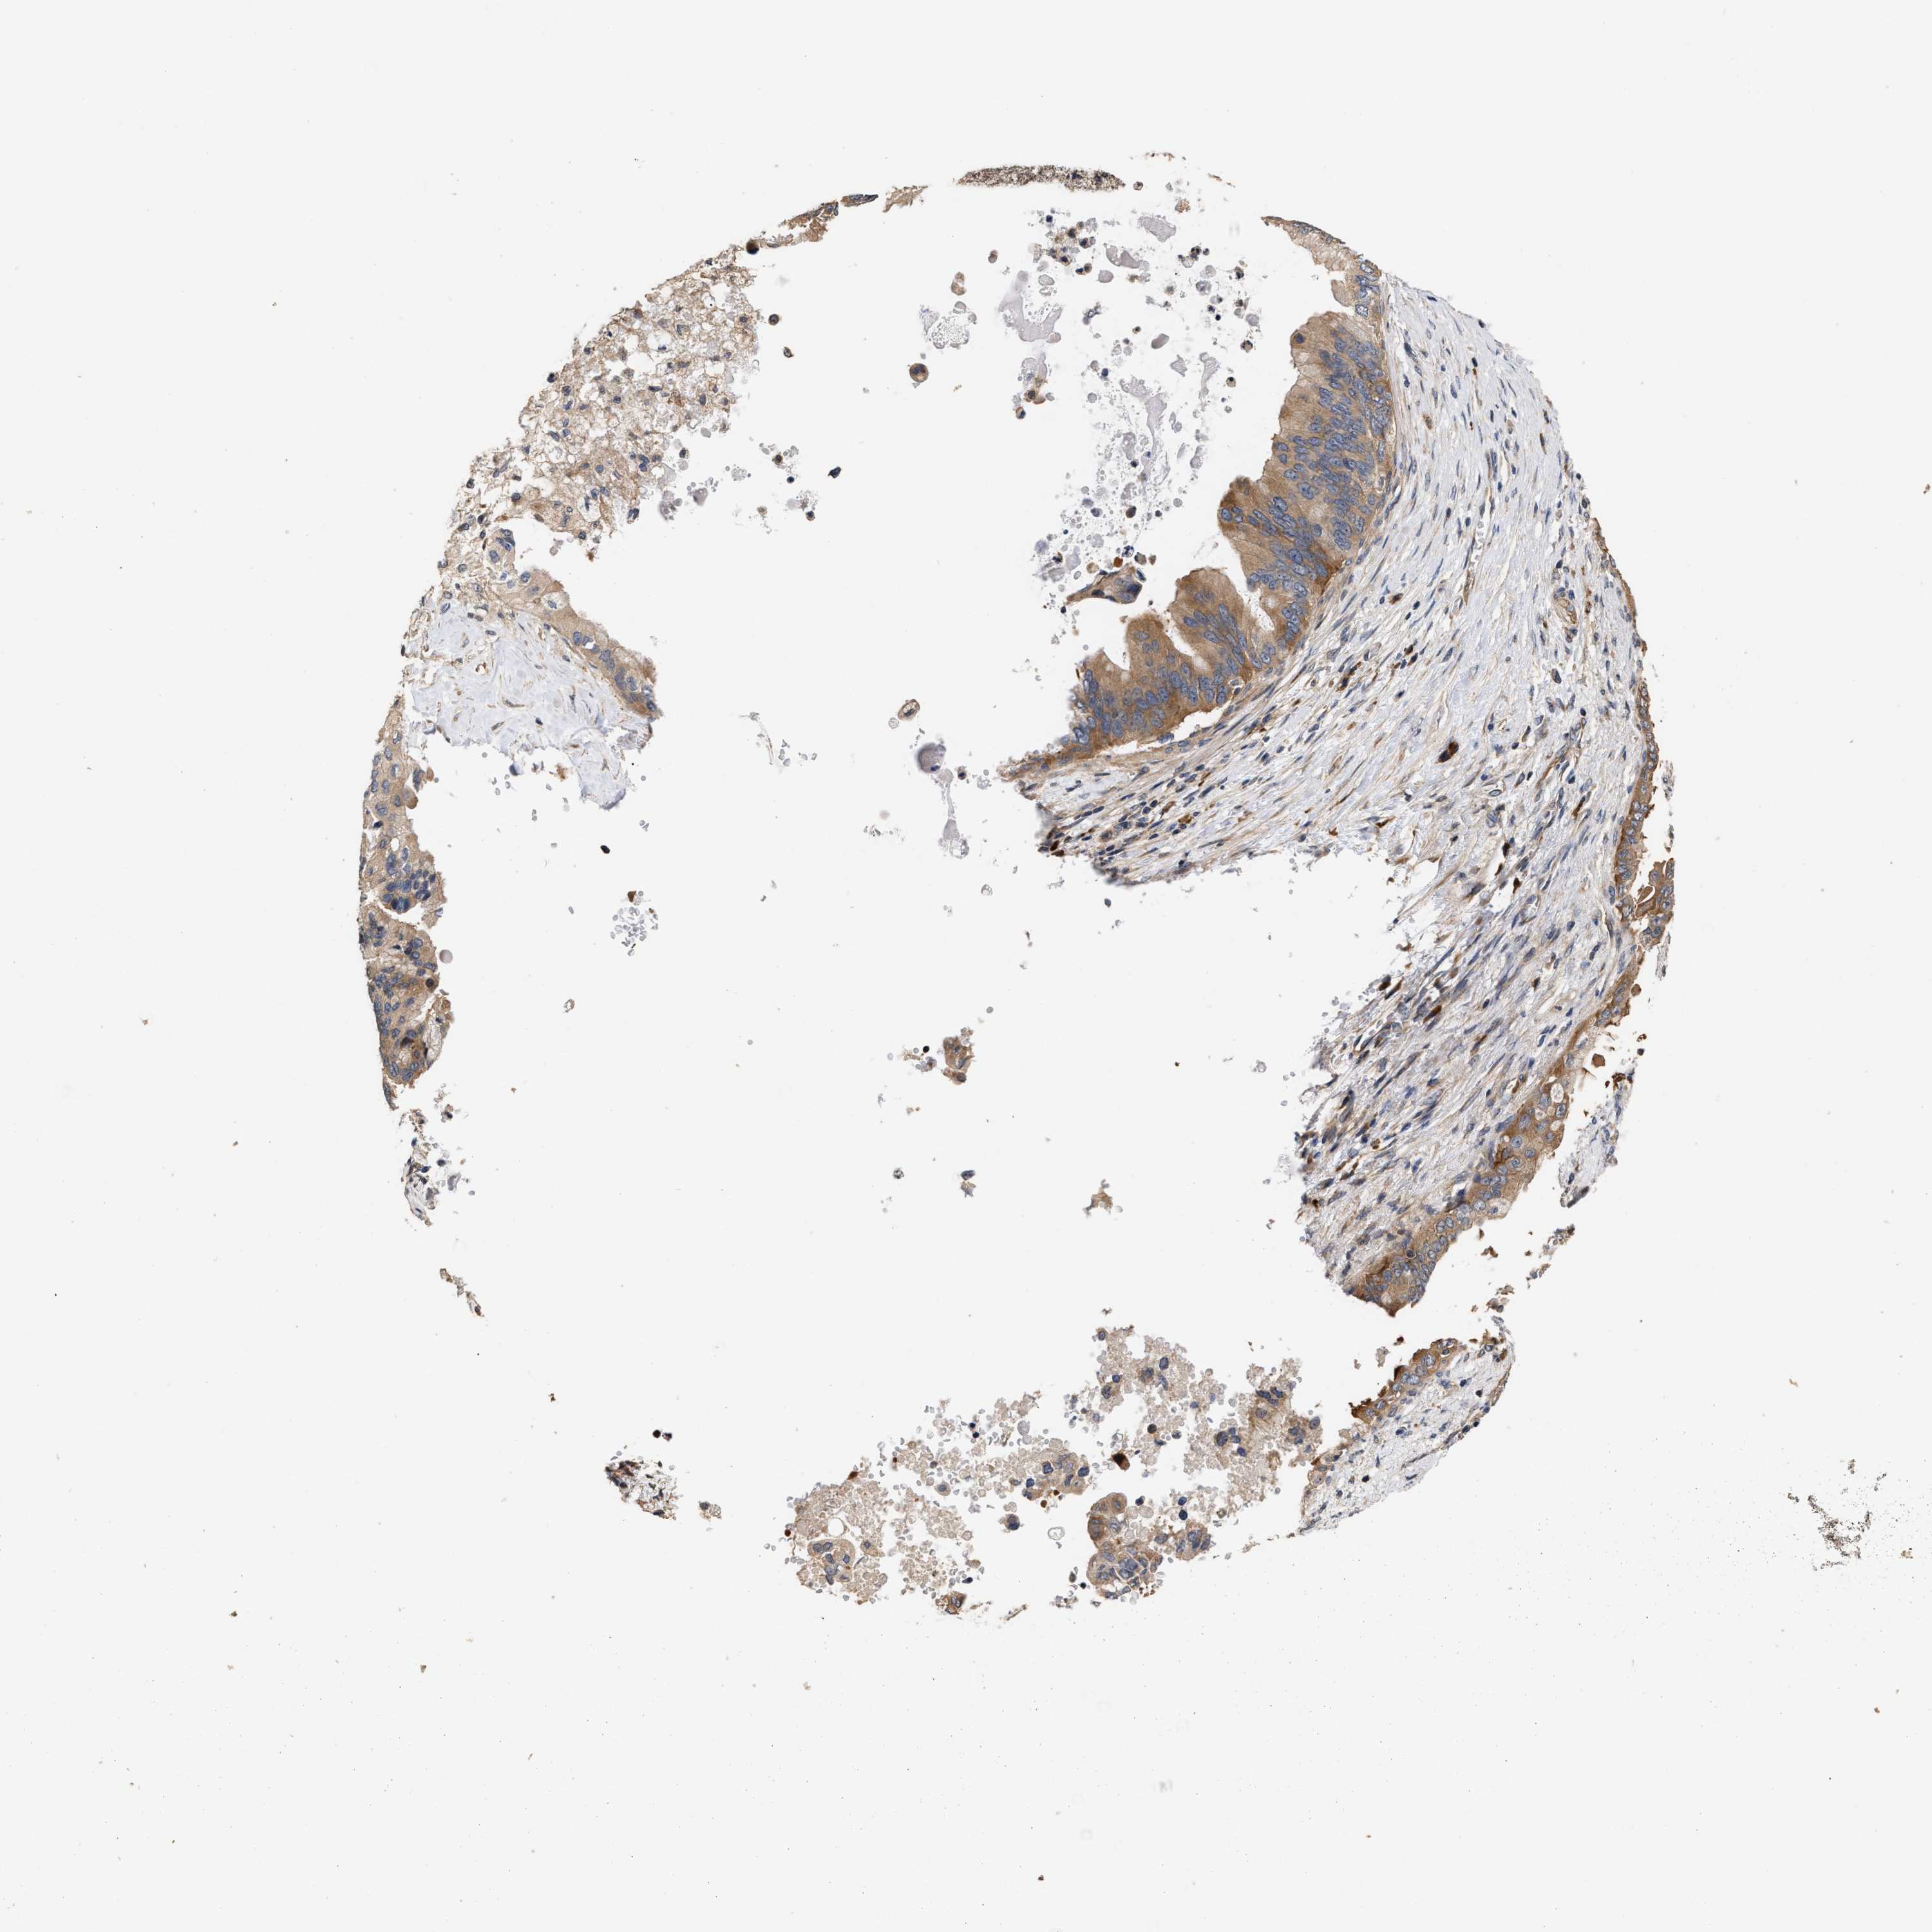

PANCREATIC CANCER - Protein expressioni

A mouse-over function shows sample information and annotation data. Click on an image to view it in a full screen mode. Samples can be filtered based on level of antibody staining by selecting one or several of the following categories: high, medium, low and not detected. The assay and annotation is described here.

Note that samples used for immunohistochemistry by the Human Protein Atlas do not correspond to samples in the TCGA dataset.

Antibody stainingi

Antibody staining in the annotated cell types in the current human tissue is reported as not detected, low, medium, or high, based on conventional immunohistochemistry profiling in selected tissues. This score is based on the combination of the staining intensity and fraction of stained cells.

Each image is clickable and will lead to virtual microscopy that enables deeper exploration of all samples and also displays staining intensity scores, fraction scores and subcellular localization as well as patient and tissue information for each sample.

Antibody HPA020430

Antibody CAB020767

Staining

High

Medium

Low

Not detected

Intensity

Strong

Moderate

Weak

Negative

Quantity

>75%

75%-25%

<25%

None

Location

Nuclear

Cytoplasmic/membranous

Cytoplasmic/membranous,nuclear

Adenocarcinoma, NOS